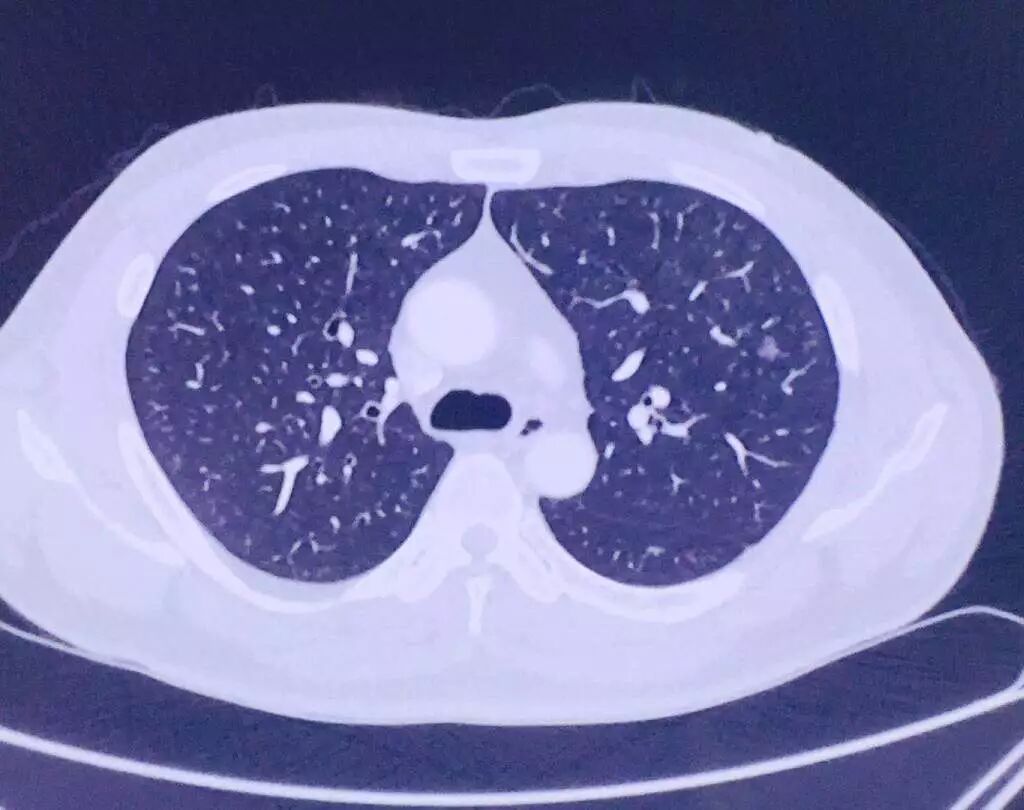

近日,泰州的王先生体检发现左肺上叶有个小结节,去当地多家医院咨询后可以微创手术切除 但要三个小切口,辗转多方打听后,王先生了解到南京市胸科医院杨如松院长这儿只要一个小切口就可以,而且只要一个约3cm的手术切口就能解决病人的肺结节问题,故来我院就诊 杨院长接诊后,仔细研读患者的胸部CT检查,其左上肺的结节直径约7mm,距胸膜缘2.3cm杨院长根据多年临床经验判断, 这很可能是一个肺部早期恶性肿瘤,确实需要手术切除。但患者的肿块位置较深,要达到在保证精确切除病灶的前提下,更多地保留病人相对完整的肺组织的目的, 初步估测,对这个病人而言,解剖性肺段切除是最佳选择! 随后,杨院长用目前最先进的软件3D一CTBA对患者肺部结节精准定位 确定病灶位于后段与前段之间,单纯的后段或者前段的肺段切除并不能解决问题 最佳方案采用左上肺联合亚段切除,既根治肿瘤、又可保留更多肺组织, 而这增加了手术难度艺高人胆大,再加上已经有单孔胸腔镜肺段切除170余例,和单孔胸腔镜联合肺亚段切除的6例基础 杨院长决定给王先生行,单孔联合亚段(S2b+S3a)切除 人体左右两侧肺共有5个叶,分为大约19个段,再分为大约36个亚段,在治好疾病的基础上, 为了最大限度保护病人的肺功能,手术从肺叶的切除到肺段的切除,再到最先进的肺亚段切除, 外科医生一直在不停的自我挑战,而从三孔行上述手术到单孔下完成上述手术,更是对胸外科医生提出更大的要求。 但为了病人的一切,杨如松院长一直没有放松对自己的要求,最近两年已经成功完成单孔胸腔镜肺段切除170余例,和单孔胸腔镜联合肺亚段切除的6例 很好的实现了既要治好病人的疾病,又成功的最大限度的保护了病人的肺功能的目的。 但实现这一目标,光靠满腔热情还不够,还得有足够的临床实践和相应的硬件设施, 肺亚段手术的技术要求很高,因为每个人的肺部都长得不一样,病灶也不会长在一个固定的、一成不变的位置上, 如果切错,后果将不堪设想。 我院胸外科利用先进的3D扫描技术,将患者肺部CT数据导入计算机,实现了肺部三维模型的重建,这个模型看上去像是分叉较多的树枝, 段支气管显示好;还可以2D与3D融合显示,从中可以更精准的判断病变方位,从而提高手术的精准性。 有了上述基础,近日王先生安全的接受了单孔胸腔镜的联合亚段切除手术按照原计划顺利进行, 整个肺的联合亚段切除只用了一个小时的时间现在患者恢复非常顺利。